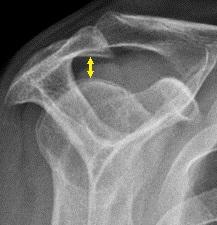

Supraspinatus outlet view X-ray, showing subacromial space measurement.

• The normal subacromial space in shoulder radiographs is 9–10 mm; this space is significantly greater in men, with a slight reduction with age.[2] In middle age, a subacromial space less than 6 mm is pathological, and may indicate a rupture of the tendon of the supraspinatus muscle.[2]